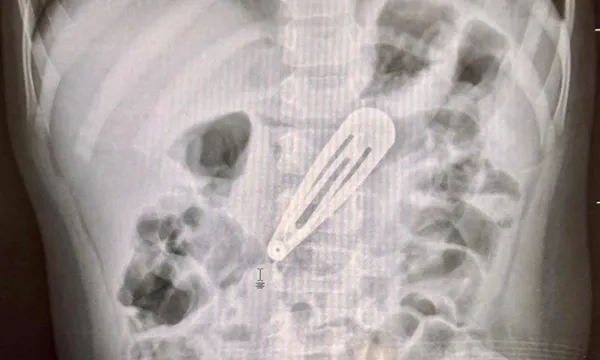

Sau khi thăm khám lâm sàng và chụp X-quang bụng, các bác sĩ ghi nhận hình ảnh dị vật kim loại nằm trong ổ bụng, tương ứng vị trí dạ dày của bé. Bé nhanh chóng được chuyển sang Trung tâm Nội soi tiêu hóa và Thăm dò chức năng để tiến hành nội soi can thiệp lấy dị vật ra ngoài.

Bác sĩ chuyên khoa I Tô Duy Thư cho biết: “Dị vật là chiếc kẹp tóc kim loại, dẹt, đầu tù, cạnh sắc, nằm ở vùng thân vị (phần giữa của dạ dày). Dù dị vật không quá nhọn, nhưng cạnh sắc và kích thước lớn dễ gây thủng rách trên đường di chuyển, đặc biệt khi di chuyển xuống ruột non – vị trí lòng ruột nhỏ, thành mỏng - có thể gây rách, thủng hoặc tắc ruột cơ học. Khi dị vật gây thủng ruột hay gây tắc ruột (thời gian dài có thể dẫn tới hoại tử đoạn ruột), nếu không tiến hành phẫu thuật kịp thời có thể dẫn đến nguy cơ tử vong”.

May mắn, chiếc kẹp tóc này chưa gây tổn thương đến niêm mạc tiêu hóa. Qua nội soi, các bác sĩ ghi nhận dị vật vẫn nằm trong dạ dày, chưa gây rách hay thủng. Dị vật được cố định bằng dụng cụ chuyên dụng và gắp ra thành công, không để lại biến chứng. Sau thủ thuật, sức khỏe bé ổn định.